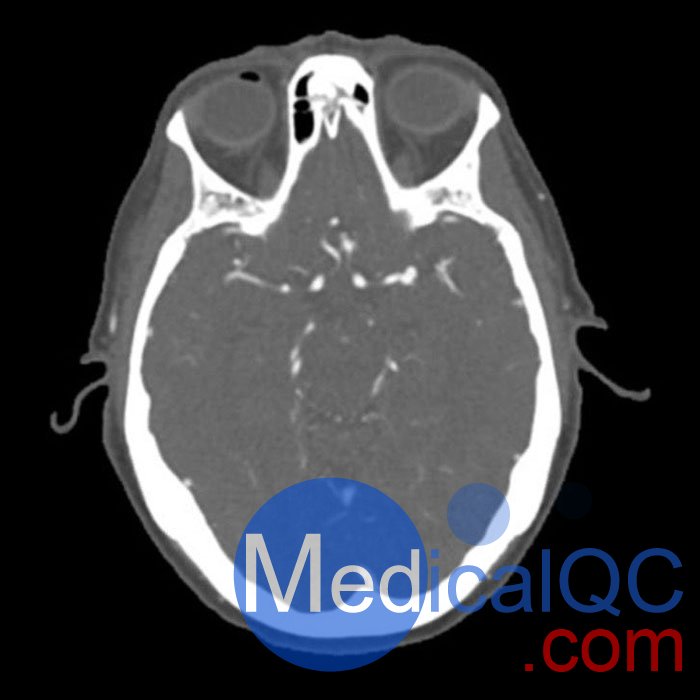

CTA是通過靜脈注射對比劑,以全身血管為檢查對象,利用CT設備進行血管成像,是目前臨床上診斷心腦血管及外周血管疾病常用的無創(chuàng)性檢查方法。

WEK50-03動脈瘤頭模,WEK50-03血管造影CTA頭模是頭部 CTA 動脈瘤模型

模擬造影劑動脈期頭部增強(CT血管造影)。 它覆蓋了頂點枕骨大孔。

該體模可用于CT(包括CBCT)評估和優(yōu)化成像性能和人工智能診斷。 這是也適合培訓目的。

WEK50-03動脈瘤頭模,WEK50-03血管造影CTA頭模規(guī)格

尺寸:約 191×218×150毫米

重量:約 2680克

基材:纖維素聚合物復合材料

最佳:120 kVp - 可根據(jù)要求調整 - 管電壓